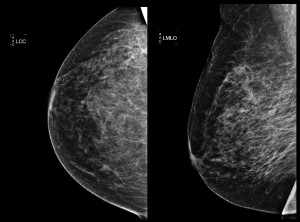

Las pacientes diagnosticadas de carcinoma mamario y que han pasado por una cirugía mamaria conservadora deben realizarse una mamografía anual. Esto es así porque este grupo de pacientes tienen un elevado riesgo de desarrollar recurrencias locales o nuevos tumores, y la mamografía es la única prueba que ha demostrado su eficiencia en la detección precoz de estas patologías.

Haz click en las imágenes para verlas ampliadas